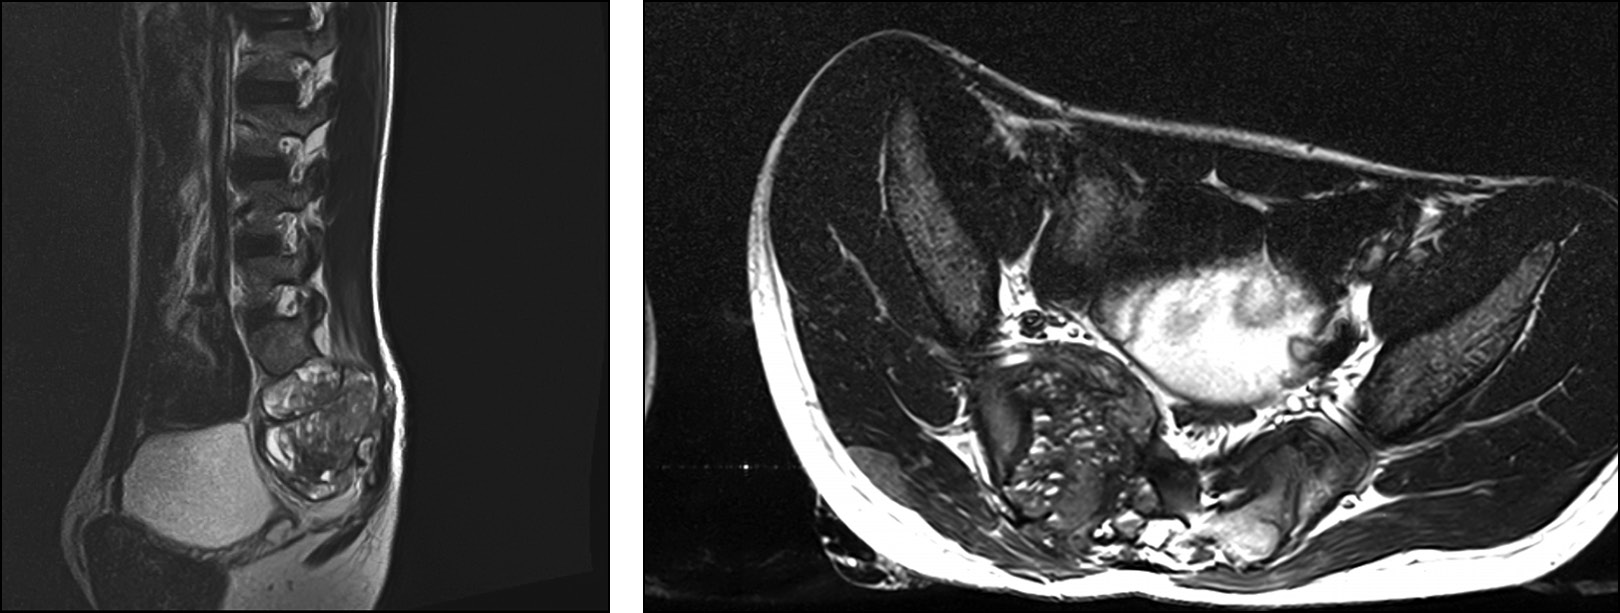

На момент первой госпитализации возраст пациента составлял 16 лет. По месту жительства выявлено новообразование крестца, выполнена открытая биопсия, гистологически поставлен диагноз — аневризмальная костная киста крестца. При первом поступлении в отделение детской костной патологии и подростковой ортопедии предъявлял жалобы на боль в области крестца до 7 баллов по ВАШ, боль иррадиировала в правую нижнюю конечность до пятки, также отмечал периодическую боль при акте дефекации, запоры. Вышеуказанные жалобы беспокоили с ноября 2021 г. с постепенным ухудшением. Представлены МРТ пациента при первом поступлении в стационар (рис. 2). По данным лучевых методов исследования отмечаются лизис костной ткани в области опухоли, компрессия невральных структур, отдавливание тазовых органов. Оболочка опухоли представлена её мягкотканным компонентом без признаков окостенения. Пункционное лечение начато в апреле 2020 г. При первичной пункции давление в опухоли составило 510 мм вод. ст., кровопотеря — 150 мл. На момент третьей госпитализации (после 4 пункций и 3 месяцев с начала лечения) жалобы на боль и неврологическая симптоматика регрессировали. Можно наблюдать признаки частичной оссификации оболочек опухоли, выстраивание костных мостиков в полости кисты через один год (после 12 пункций) с начала лечения пациента. На 13-й пункции давление менее 120 мм вод. ст., кровопотеря менее 50 мл. В связи со снижением активности принято решение о частичной резекции задней стенки опухоли и дренировании глубоких отделов АКК. Через 6 месяцев введён костнопластический материал Коллап-Ан в полость кисты. На КТ-исследовании через один год после открытой частичной резекции задней стенки опухоли и дренирования глубоких отделов АКК и через 6 месяцев после пункционного введения костнопластического материала определяется постепенное восстановление костной ткани крестца, полное окостенение оболочек кисты. Как и в большинстве случаев при восстановлении костных структур, отмечается формирование просвета позвоночного канала и анатомии крестцовых отверстий по принципам памяти костной формы, что отчётливо визуализируется на контрольных КТ-исследованиях. При динамическом наблюдении и на момент повторных госпитализаций пациент отмечал полный регресс болевого синдрома и неврологической симптоматики уже после четвёртой манипуляции. Данных о продолженном росте патологического процесса получено не было. Пациент проходит этапное пункционное лечение. Динамика КТ-исследования пациента 1 представлена на рис. 3.

Рис. 2. МРТ на момент первой госпитализации. Киста представлена гигантской опухолью со множеством камер с разными уровнями жидкости. Определяется компрессия невральных структур, сдавление органов таза.

Fig. 2. An MRI scan at the time of the initial hospitalization revealed a cyst in the form of a large tumor with multiple chambers containing different levels of fluid. The MRI also showed compression of neural structures and pelvic organs.